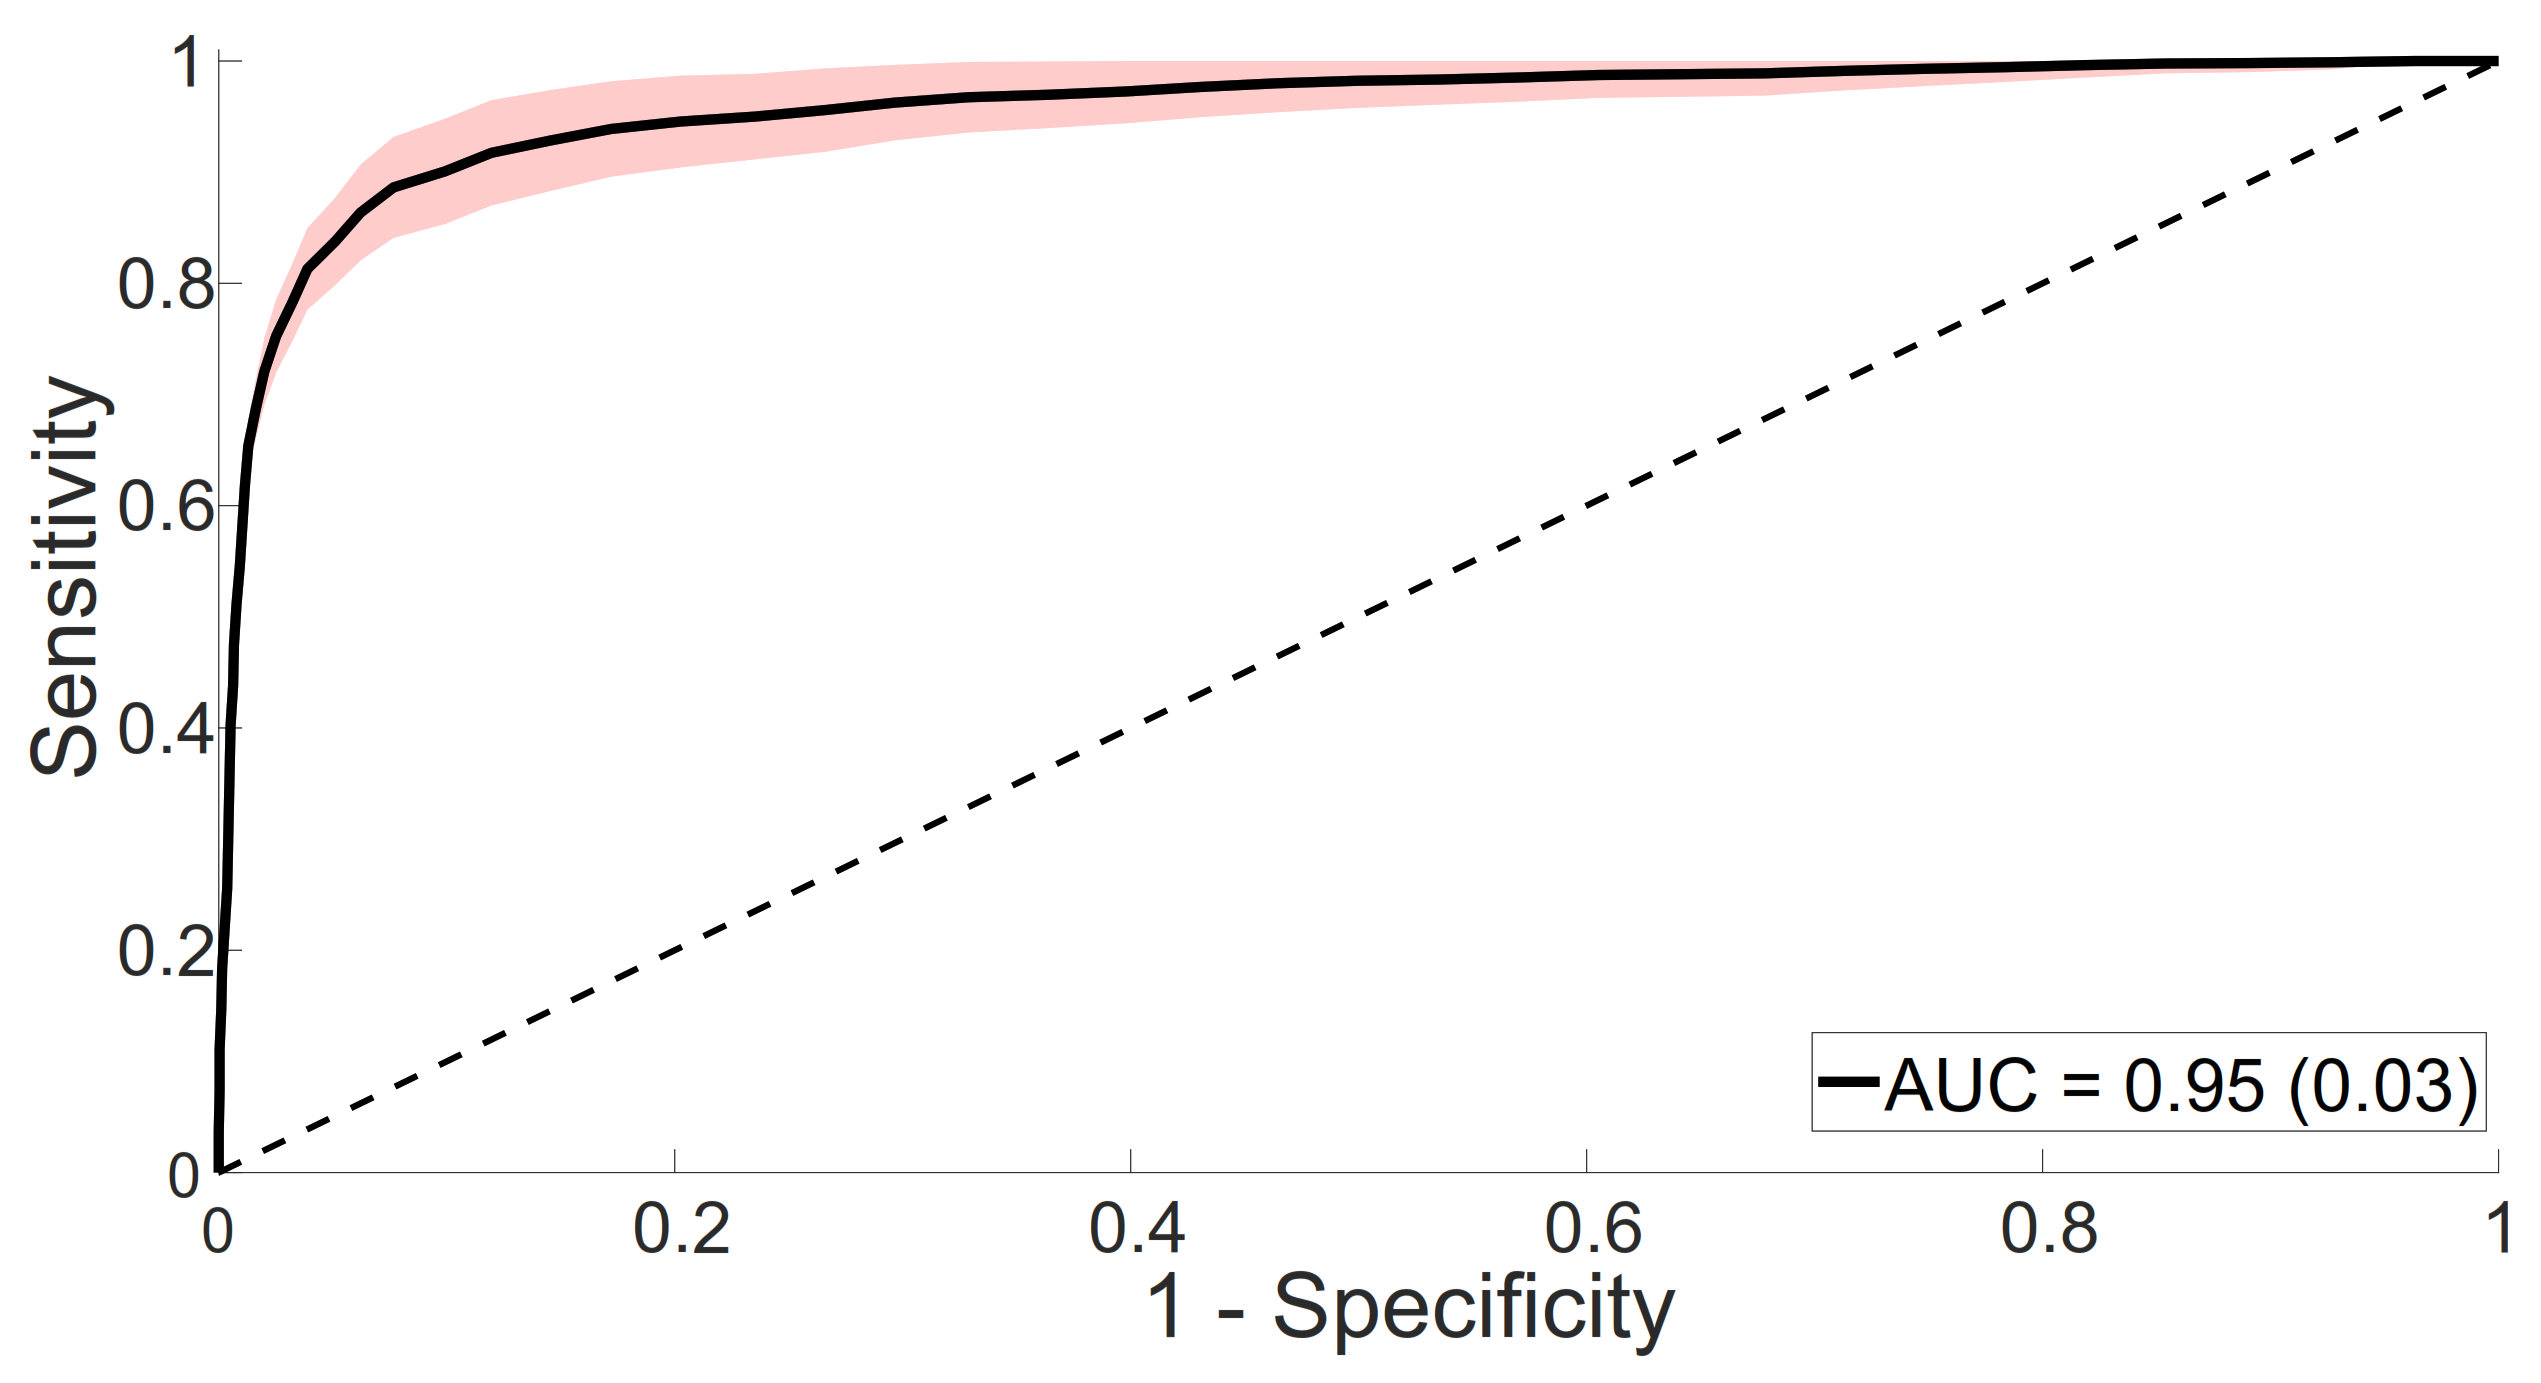

4.1. Myocardial Abnormality Detection

4.1.1. Model Selection

4.1.2. Classifier Evaluation